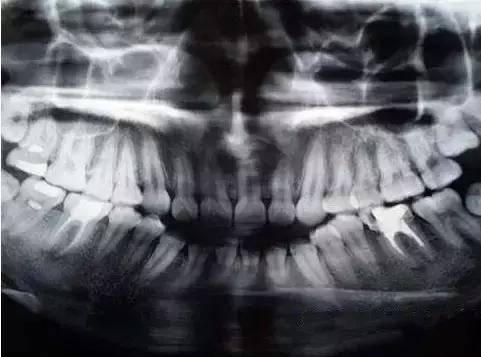

其次可以看看X光片子,爛到牙髓是有陰影的。如果X光片上,牙已經有了大洞,而且拍完片子醫生也說要根管治療,那麽(me) 還是抓緊吧~